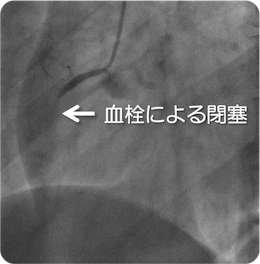

心筋梗塞を発症した際の冠動脈造影と治療後

血栓をカテーテルで吸引した上でバルーンにて拡張。更にステントを留置し、血流が再開しています。